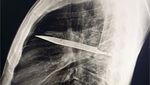

Jakarta - Begini penampakan pisau yang menancap di dada seorang pria di Tanzania. Pasien baru menyadari di tubuhnya ada pisau 8 tahun kemudian.

Foto-foto Penampakan Pisau Menancap di Dada, Pasien Sadar Setelah 8 Tahun